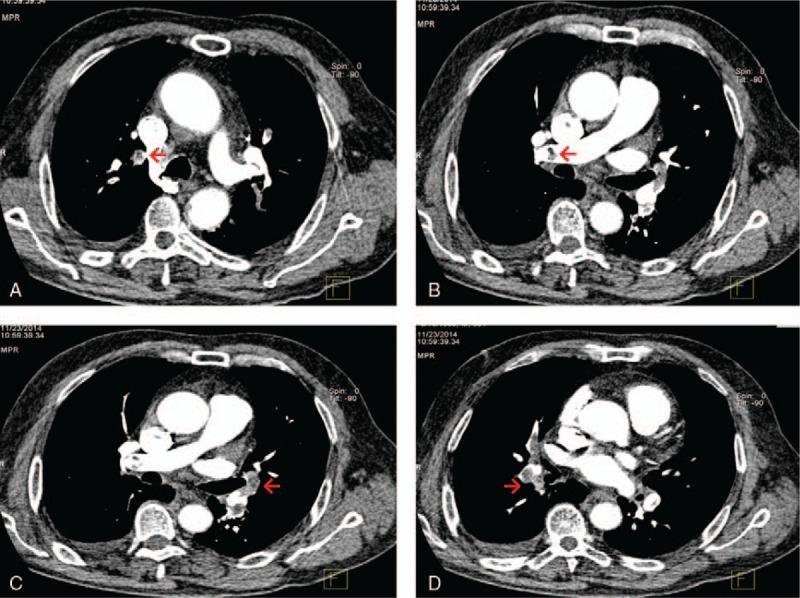

We described a 59-year-old man who presented to emergency department complaining of chest pain.

He was suffered acute myocardial infarction (MI) and pulmonary embolism (PE) simultaneously.

Dual antiplatelet therapy, statin, and low molecular weight heparin were administrated during his stay. The searches for cancers, autoimmune diseases, and hematologic diseases were unremarkable, ruling out a hypercoagulable state. Subsequent ultrasound scan revealed a thrombus in a vein of the lower left extremity. Thus, paradoxical embolism was highly suspected.

Paradoxical embolism is a rare cause of acute MI, which may have occurred in our patient. This was evidenced by a previously unrecognized patent foramen ovale (PFO) with a right-to-left atrial shunt detected using contrast transesophageal echocardiography.

我们描述了一名59岁男性,他因胸痛到急诊科就诊。

他同时患有急性心肌梗死(MI)和肺栓塞(PE)。

住院期间给予双联抗血小板治疗、他汀类药物和低分子肝素。对癌症、自身免疫性疾病和血液系统疾病的检查未发现异常,排除了高凝状态。随后的超声扫描显示左下肢静脉有血栓。因此,高度怀疑为反常栓塞。

反常栓塞是急性心肌梗死的罕见原因,可能在我们的患者中发生。经食管对比超声心动图检测到先前未被识别的卵圆孔未闭(PFO)伴右向左心房分流,证明了这一点。